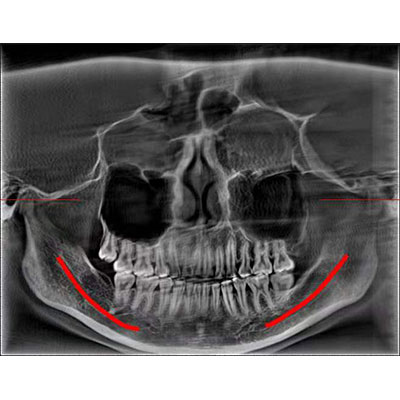

通过三维容积影像,提取高清口腔全景影像。

专有图像校正技术,去除金属伪影,提高图像分辨率。